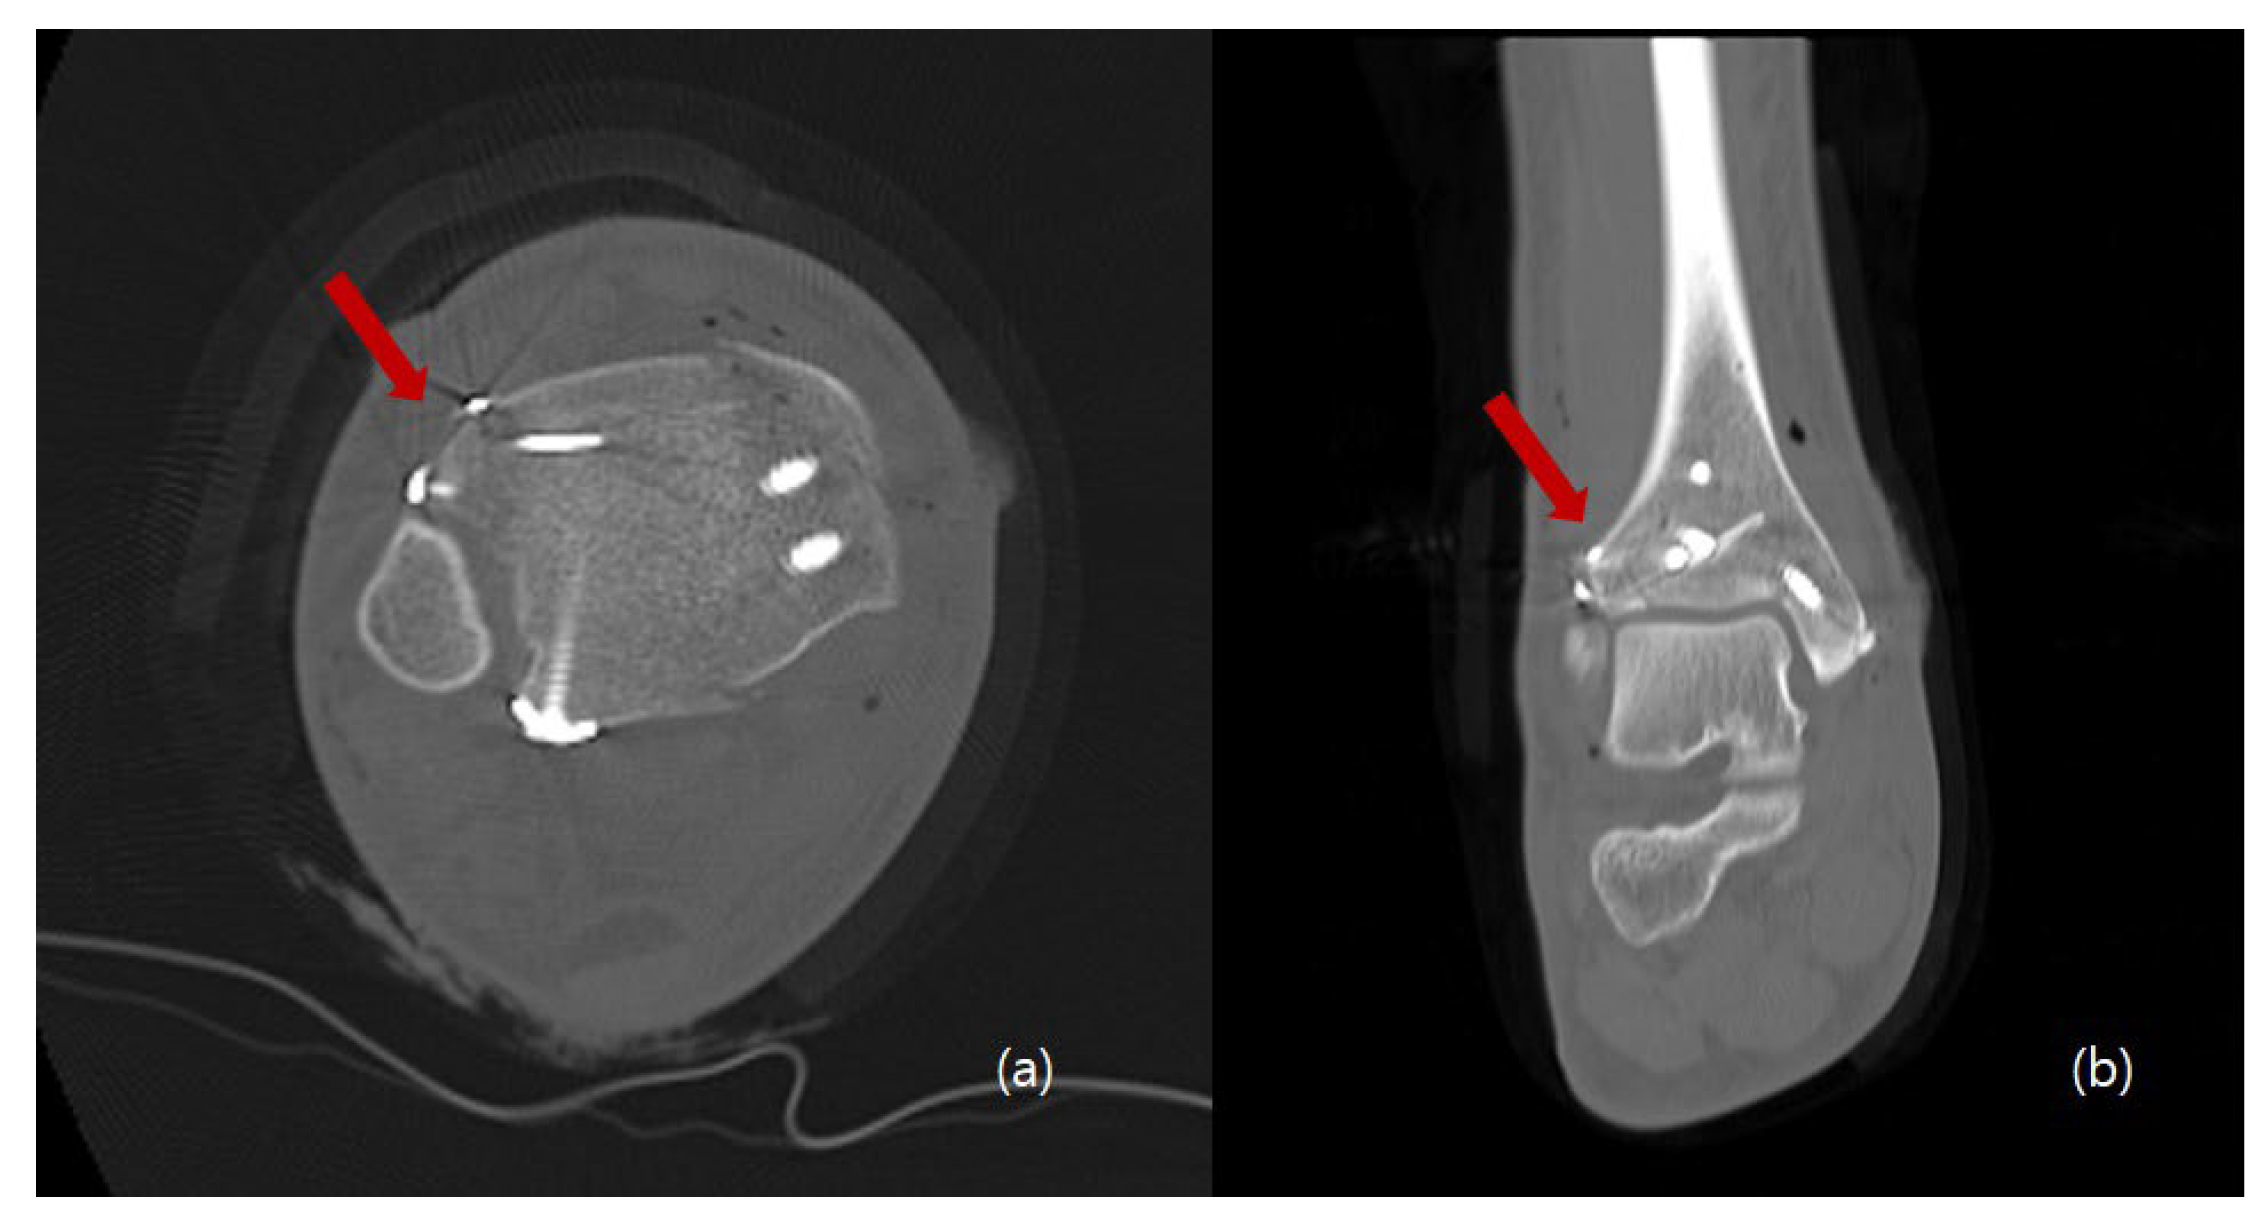

2. Surgical Technique